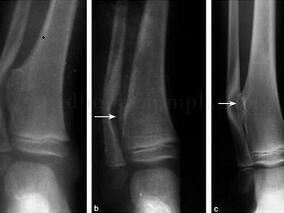

1小时条评论有时骨软骨瘤术后再发生,并非严格意义上的肿瘤复发,而是之前手术并未彻底切除,残留部分继续生长所致。造成骨软骨瘤术后再发生的因素有哪些?为什么儿童期实施骨软骨瘤手术复发率较骨骼发育成熟后手术复发率高?希望以下两例病例能为您带来启发 (1)病例介绍 病...